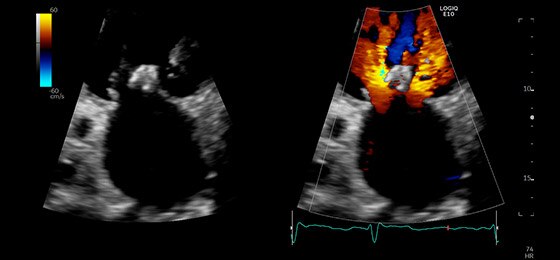

Dual Color Flow Jets, M5Sc-D

Alax CF Mitral and Aortic Valves, M5Sc-D

Apical 4CH CF Tricuspid Valve, M5Sc-D

Color Through Pulmonic Valve, M5Sc-D